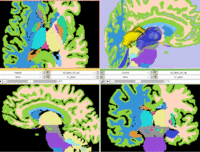

Registration Results

unregistered

after ICP Surface Registration + Clipping

Discussion: Registration Challenges

• Because the structures of interest are a very small subset of the image without distinct grayscale contrast

• the two atlases represent different anatomies and hence some residual misalignment is inevitable

• the two labelmaps have different resolutions and different smoothness of structure outlines. Some need filtering to remove spurious surface details that would distract the registration algorithm

Discussion: Key Strategies

• Because the structures of interest are a very small subset of the image without distinct grayscale contrast, we co-register surfaces rather than intensity volumes